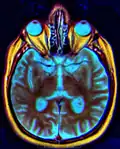

IRM de Chiasma optique.